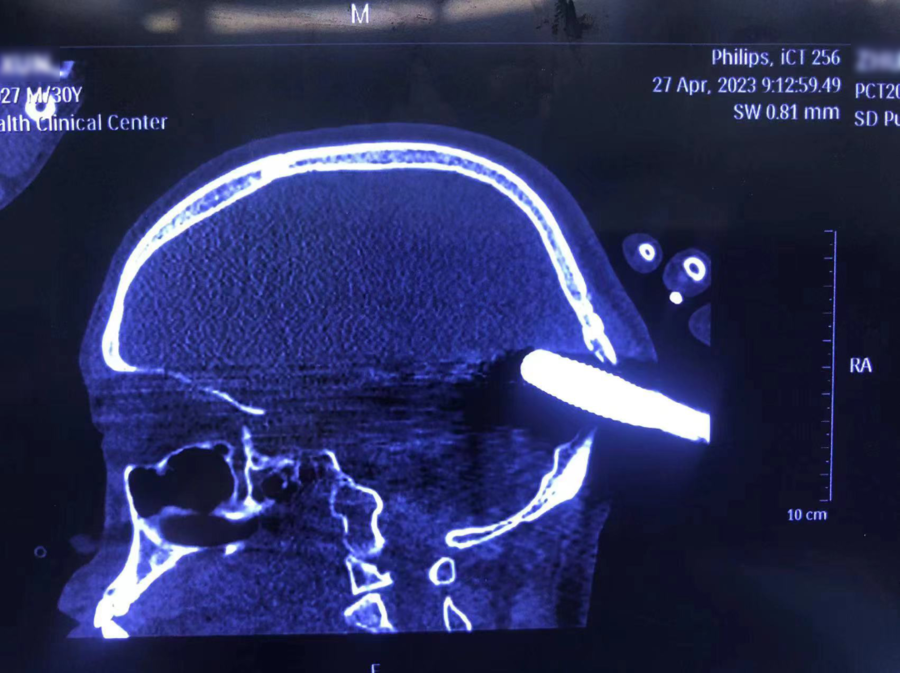

患者颅脑CT检查提示钢筋突破颅骨、硬脑膜,直接插入脑组织内,钢筋贯穿颅骨位置位于颅内大血管交汇处,且钢筋前段临近脑干,轻微的移动都可能导致血管损伤,引起颅内大出血危及生命。